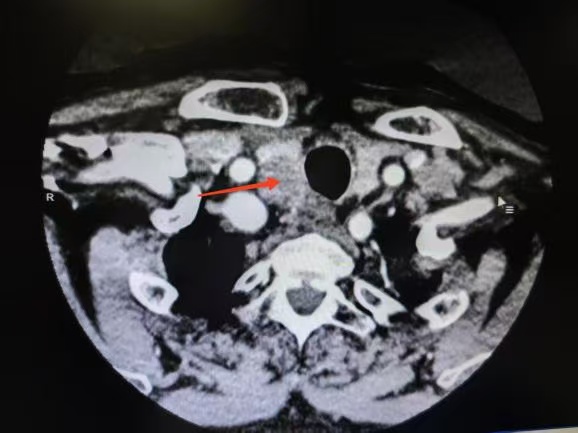

CT箭頭所示:右側(cè)甲狀腺腫瘤